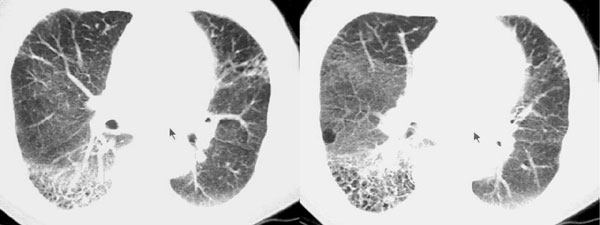

以下是引用dyqct在2006-9-10 13:57:00的发言:[br]右肺下叶呈蜂窝状改变;左且舌段亦见多数条状高密度影,边界不清,下叶见多数磨玻璃样影,并可见胸膜下线。[br]考虑:间质纤维化(后期改变,蜂窝肺)伴感染、支气管扩张。

以下是引用袁张锋在2006-9-10 21:28:00的发言:[br]右肺下叶呈蜂窝状改变;左且舌段亦见多数条状高密度影,边界不清,下叶见多数磨玻璃样影,并可见胸膜下线。[br]考虑:间质纤维化(后期改变,蜂窝肺)伴感染、支气管扩张。